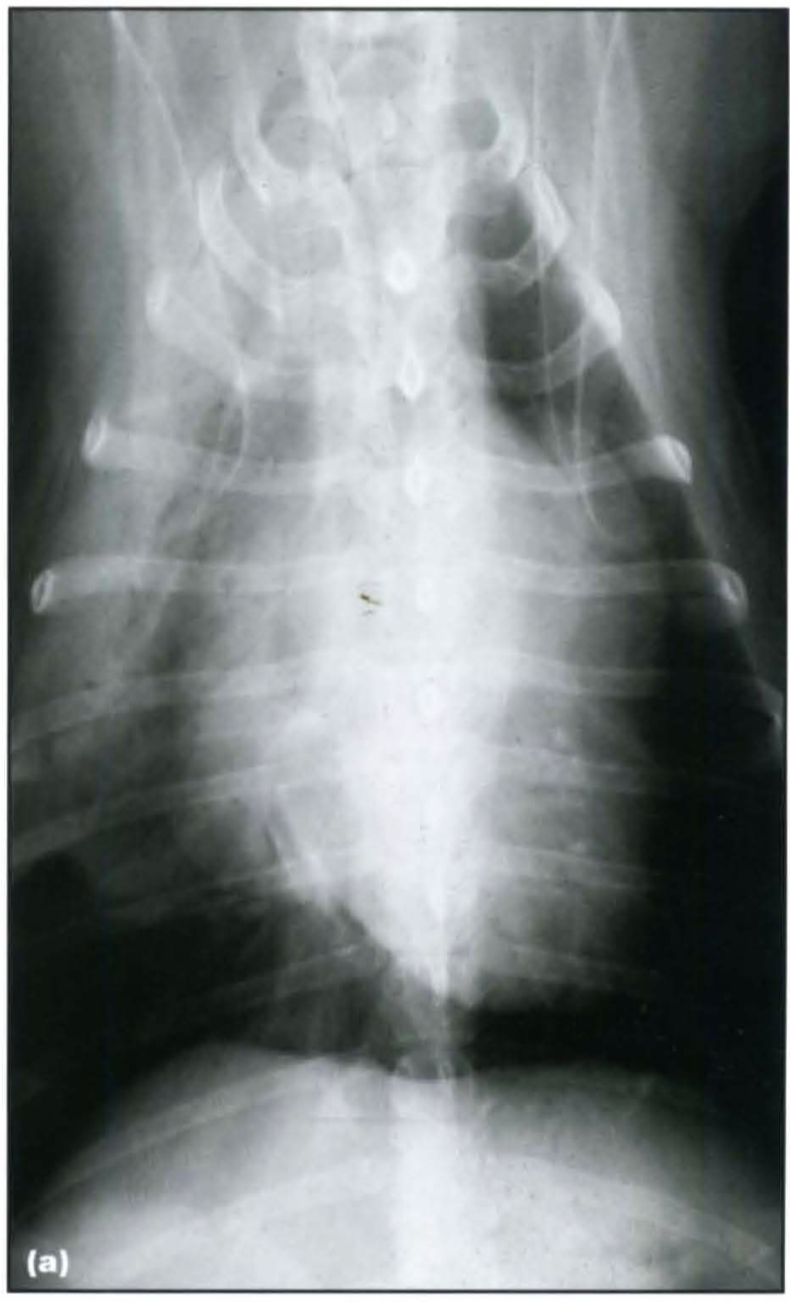

Primary ciliary dyskinesia (PCD), also known as immotile cilia syndrome, is a diverse group of inherited structural and functional abnormalities of the respiratory and other cilia, which results in recurrent respiratory tract infections in the dog. More specifically, PCD is an inherited defect in microtubule formation, affecting cilia of the respiratory and urogenital tract and the auditory canal.

Typically PCD is diagnosed in young purebred animals with a reported higher incidence in the Bichon Frise. The condition may be seen in mixed breed dogs and also in cats.

There is a relatively high prevalence of a respiratory disease and the phenotype is almost identical to PCD in humans. The respiratory manifestations include chronic rhinitis , bronchitis and severe pneumonia with or without bronchiectasis. Affected animals are presented with recurrent chronic nasal discharge, productive cough, respiratory distress and exercise intolerance. Additional findings are infertility, hydrocephalus and loss of hearing.

Radiography:

Computed tomography: